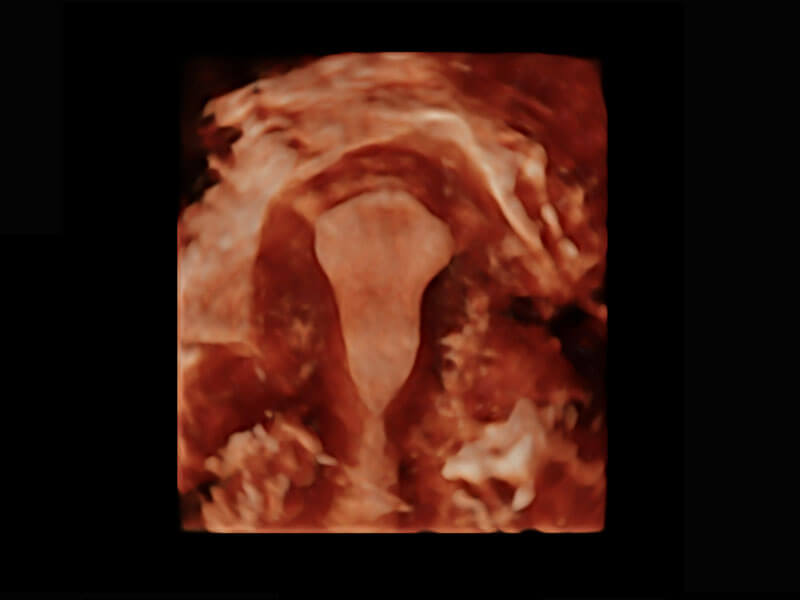

中晚孕筛查

P60提供简单易学易用的高端诊断工具,为您中晚孕筛查提供快速清晰的解剖信息。